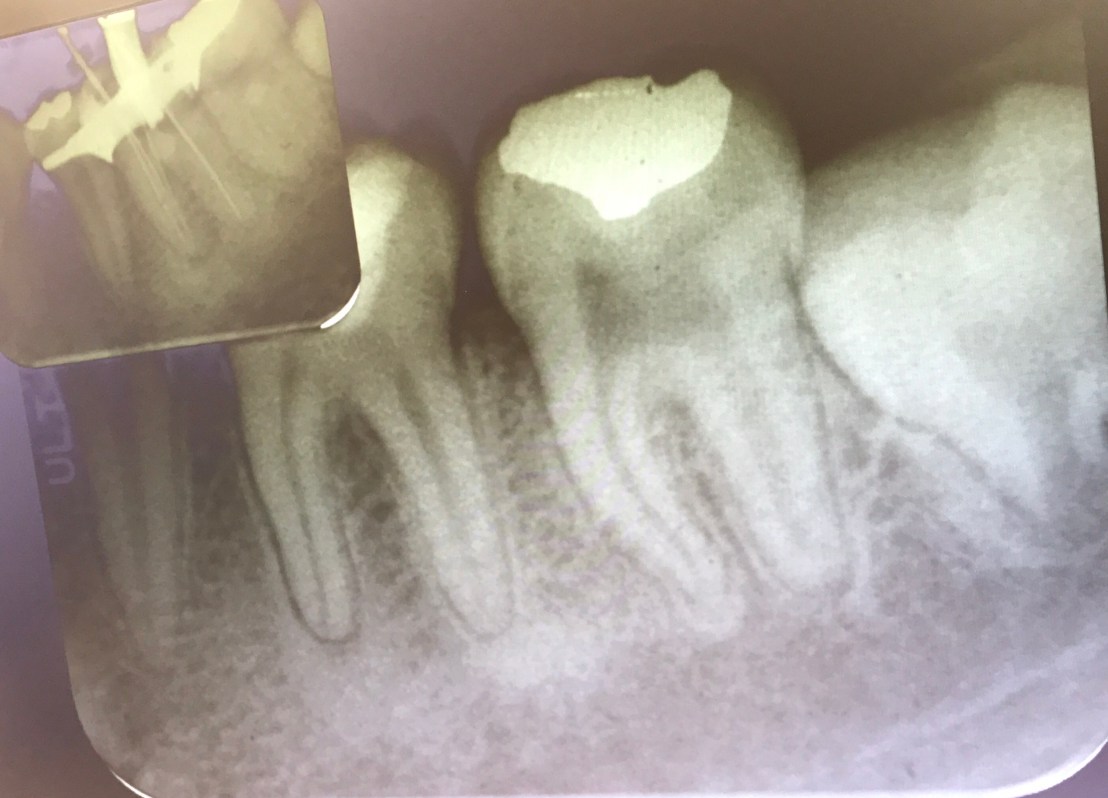

ฟัน #36, 46 คือฟันที่ท่านอาจารย์เตรียมไว้ให้สำหรับการฝึกการรื้อเครื่องมือและการซ่อมรอย perforate ในช่วงบ่าย

case แสดง Root canal retreatment ฟันซี่นี้มี Post หักที่ Distal root

อันนี้คือ case จริงครับ ส่วนที่ Outline ไว้ตรงกลางคือ รอย Perforate